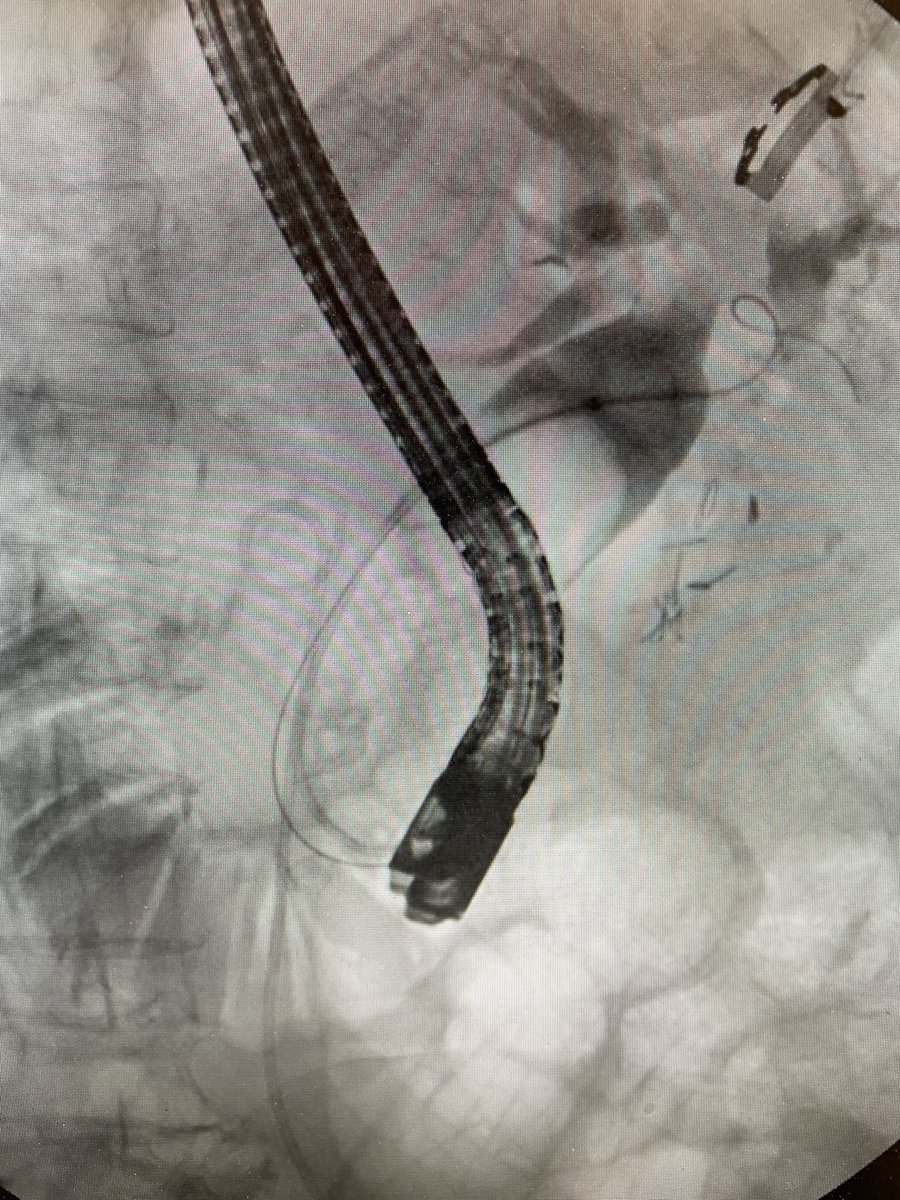

@DouglasAdlerMD

Douglas G. Adler MD, FASGE, FACG, AGAF

3 days

Now THAT is a big common bile duct stone! #gitwitter #surgery @Stentingwoman @EUSandEndoscopy @DavidDiehlMD

4

10

68